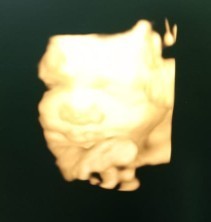

Bun sharing dong,, gimana ya caranya naikin BBJ kurang dengan makanan yang sehat. Tadi siang USG, usia kandungan 34 wek 4 day BBJ cuma 1.833kg kata dokter kurang 500gram lagi. Dan perkiraan HPL nya jadi mundur yang tadinya 12-22 Januari jadi 2 Februari, kan tambah galau Bun😭😭😭. Terus waktu buat naikin BBJ nya cuma sebulan🥺🥺. Bagi pengalaman nya ya Bun.. Terimakasih🙏🏻🙏🏻🙏🏻 #seriusnanya #bantusharing #ingintahu #pleasehelp